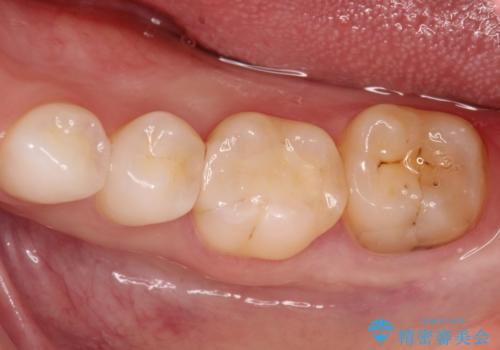

今回用いたオールセラミッククラウンはジルコニアフレームという白い素材の上にセラミックを盛っているため、審美性が非常に高いのが特徴です。

また、ジルコニアは人工ダイヤモンドの材料にも使われているほど高い強度を持っており、そのためオールセラミッククラウンは審美性だけでなく、奥歯やブリッジの補綴も可能とするクラウンです。